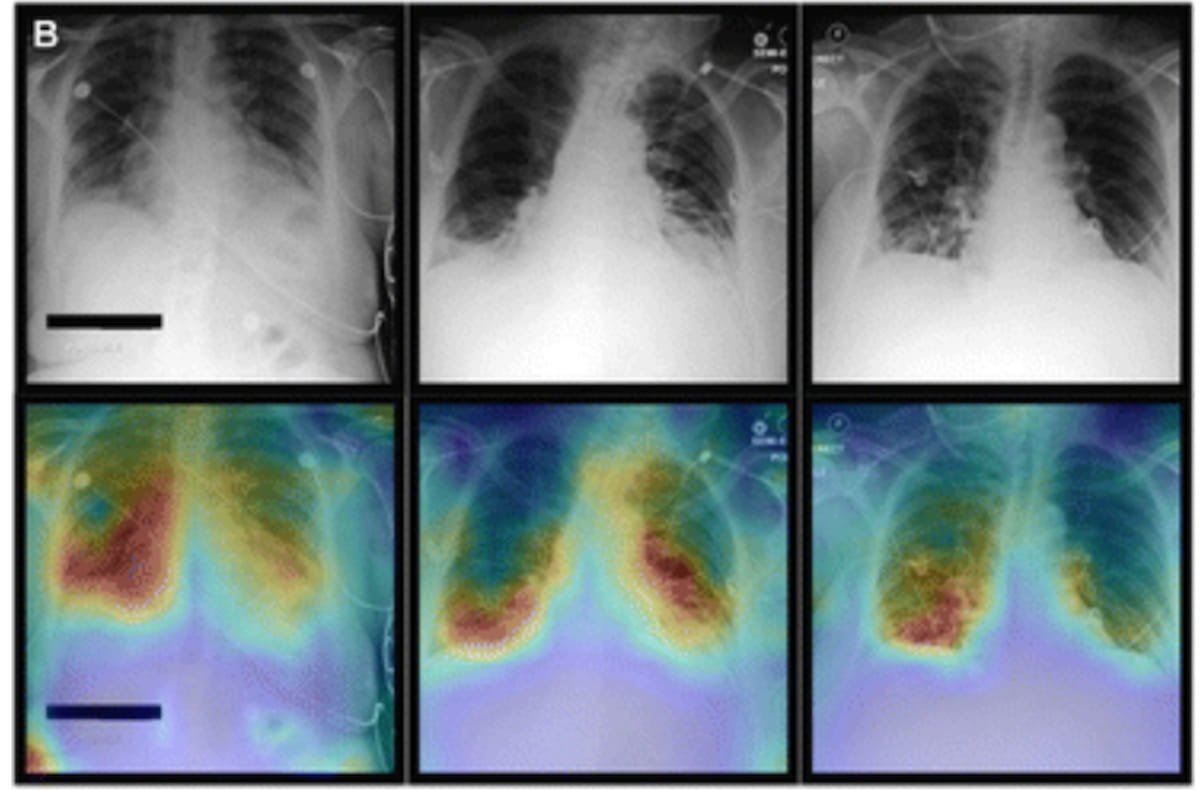

In a multicenter study examining four commercially available artificial intelligence (AI) software products for chest X-rays in over 2,000 patients, researchers found sensitivity rates ranging between 33 to 61 percent for vague airspace disease and 9 to 94 percent for small pneumothorax and pleural effusion.